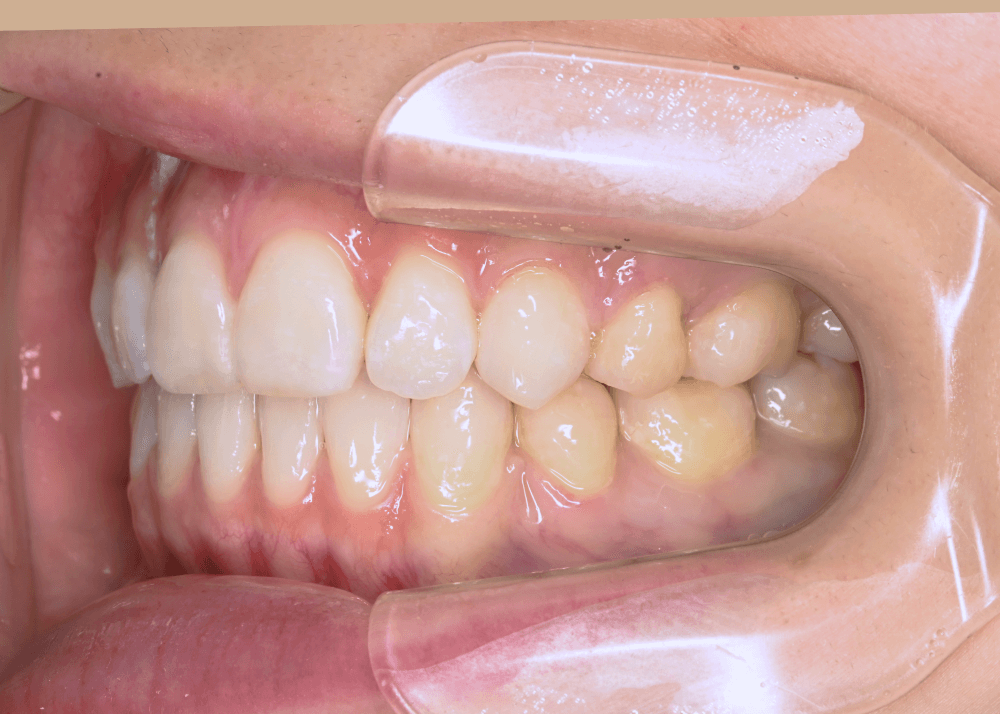

装置についてーハーフリンガル矯正ー

装置は、上あごは裏側、下あごは表側にワイヤー装置を装着する「ハーフリンガル矯正」を選択しました。

笑った際に目立ちやすい上あごの装置を裏側にすることで、審美性に配慮しながら治療を進めています。

治療後は、気にされていた「口ゴボ(口元の突出感)」が改善され、自然でバランスの良い口元になりました。

隙間のあった前歯も、しっかり噛み合うようになっています。

治療後(32か月)